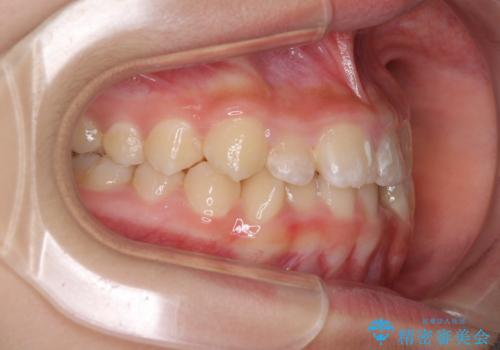

上顎骨の幅が下顎骨よりも小さいので、拡大装置により骨幅を広げて上下関係を改善し、その後インビザラインにて歯並びを整えることとしました。

上下の骨幅を改善したことで、スムーズに歯列矯正を行うことができました。